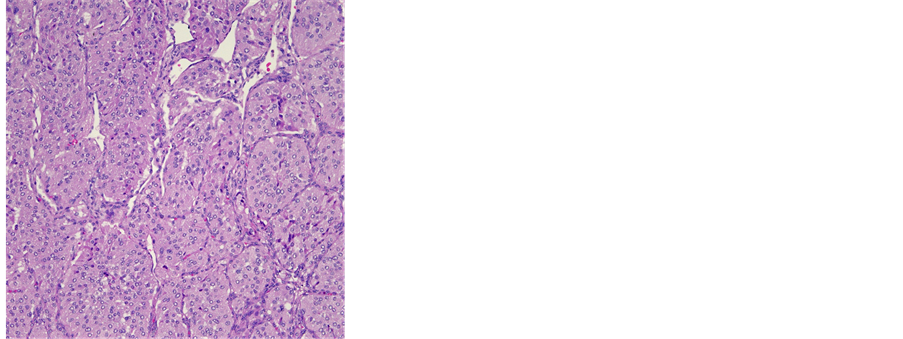

Histopathologically, the gross specimen consisted of a round to ovoid encapsulated mass of 6.4 cm in diameter, with a predominantly homogeneous, focally fibrotic cut surface. Light microscopy showed a solid neoplasm composed of a monomorphous population of round to polygonal cells with amphophilic, finely granular cytoplasm. The lesion’s architecture displayed a conspicuous nested (“Zellballen”) pattern throughout (Figure 3(a), Figure 3(b)). Mitotic activity was virtually absent, and neither extracapsular vascular invasion nor necrosis was noted. Nevertheless, focal encroachment upon the adjacent left atrial musculature was noted at the tumor’s periphery (Figure 3(c)). Immunohistochemistry confirmed expression of the neuroendocrine markers chromogranin A and synaptophysin, while the Zellballen architecture was highlighted by staining for S100 protein in sustentacular cells. Of note, tumor cells exhibited intense staining for SDHB (Figure 3(c)).

Figure 3. (a) Histological features of a paraganglioma. Note the organoid architecture (“zellballen”) arranged around ectatic, sinusoidal blood vessels. The cubic to polygonal tumor cells presents a partially amphophile, partially eosinophilic cytoplasm, moderate anisokaryosis and no mitotic activity (HE × 10); (b) Focal invasion of the left atrium. Several areas were noted, where single cardiac myocytes were surrounded by tumor cells, hence a focal invasion of the heart was postulated (HE × 40); (c) Immunohistochemical reaction with SDHB: 100% of the tumor cells presented a strong cytoplasmatic reaction (×10).